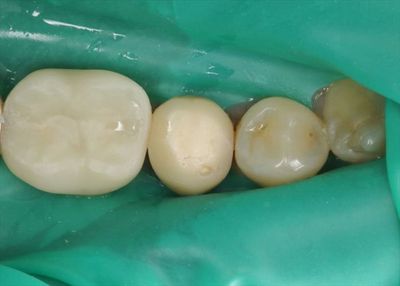

画像中央:右下第二小臼歯にレジン前装冠がセットされています。

レジン前装冠とは金属フレーム表面に歯の色のレジン(プラスチック)を盛り付けて

歯のような見た目にしているかぶせものです。

ラバーダムを装着して、まずはレジン前装冠を除去しました。

表面に白く見えるのは、かぶせものを合着していたセメントです。

内部には金属のネジ状のスクリューポストが支柱として入っており、

かぶせものの金属と触れていた部分のセメントが黒く変色しています。